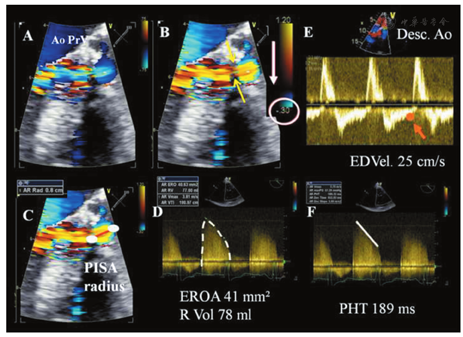

应用彩色多普勒血流可从多个切面观察舒张期流入LV的主动脉瓣反流束。早期研究对AR严重程度的界定多集中在对彩色血流束的特征性描述方面[14,20]。由于血流动力学状态、仪器设置、接受反流的心腔特点、偏心性射流、射流束冲击心腔壁的差异以及来自阅图者的差异,利用反流束的面积和长度判断反流严重程度的方法存在明显的局限性[140]。鉴于彩色反流束的面积和长度与人工瓣AR的程度相关性较差,因此不推荐用于人工瓣AR的定量评价[20]。胸骨旁长轴切面测量的反流束直径/LVOT直径,以及胸骨旁短轴切面贴近人工瓣膜下方测量的反流束面积/LVOT面积,可用来评价中央性反流的严重程度(图11)。反流束直径/LVOT直径>65%提示为重度反流[141]。然而,该方法在偏心性或新月形反流的情况下可能高估反流的严重程度,而在反流束冲击LVOT壁或二尖瓣前叶的情况下可能低估反流严重程度。

对瓣周性AR的半定量评价,需在缝合环水平的短轴切面仔细显示射流束的颈部,以精确定义其周向范围,可用反流束周长占整个缝合环周长的百分比表示反流的严重程度(<10%为轻度,10%~29%为中度,≥30%为重度)(图16)[14,125,142]。然而,这一方法受偏心性反流方向和反流束形状不规则的限制。人工瓣膜的摇摆运动常常提示瓣环开裂>40%,并造成重度反流[143]。在多个切面上观察瓣周反流起始部的宽度也有助于评价反流程度。

由于人工瓣环或支架造成的强回声声影,缩流束宽度(反流束穿过主动脉瓣口的宽度或有效反流面积)在长轴切面上难以正确测量,而在存在多个反流束、反流口形状不规则或瓣周反流的径向扩展等情况下,其测量是不准确的[64]。测量缩流束宽度有助于区分轻度和重度的人工瓣AR。采用Nyquist极限50~60 cm/s时,缩流束宽度<3 mm为轻度AR,而缩流束宽度>6 mm则提示为重度AR。

通常在机械性人工主动脉瓣中难以采用基于近端等速表面积法(PISA)进行定量评价[144,145]。当在存在中央性反流的人工生物瓣膜中采用PISA法时,常常在心尖三腔心或五腔心切面或胸骨旁长轴切面获取血流汇聚带的图像。PISA的半径在舒张期第一血流混叠层进行测量[20]。采用标准公式计算R Vol和EROA。EROA ≥ 30 mm2 或R Vol≥ 60 ml表明重度人工瓣AR。

频谱多普勒参数受人工瓣膜位置及相关的声影和伪影的影响较小,故可用于人工瓣AR的评估。在心尖五腔心切面获取人工瓣AR的CW多普勒频谱最佳。努力调整多普勒声束角度以最大限度降低与超声束角度相关的测量误差。对于偏心性反流束,右侧胸骨旁切面获得的图像信息更佳。可用CW多普勒频谱测量的PHT来评估人工瓣AR的严重程度,当PHT<200 ms时为重度反流,PHT>500 ms则表示为轻度反流。然而,PHT在中间区域时(200~500 ms)其特异性较低,因为受其他变量如心率、LV顺应性和压力、AR发生的急慢性程度(如在急性AR时,不管AR严重程度如何,PHT通常比较短)等的影响[146,147]。在降主动脉测量舒张期逆向血流时:1)取样容积置于左锁骨下动脉起始部的远端;2)PW多普勒角度与主动脉长轴平行;3)将多普勒滤波设置下调至最低以检出低速血流(<10 cm/s),放大速度标尺设置至60~80 cm/s以便更准确地测量舒张末期流速。轻度的反流仅测及舒张早期的短暂逆向血流。随着反流程度的加重,舒张期逆向血流的持续时间和血流速度随之增加。降主动脉内测及全舒张期逆向血流表明AR至少为中度,当舒张末期逆向血流速度>20 cm/s时应怀疑为重度AR[148]。该参数的主要局限性在于其受主动脉和LV顺应性的显著影响。老年患者由于主动脉僵硬度增加,在微量或轻度AR时可能出现全舒张期逆向血流。

R Vol可采用流经LVOT的每搏量(或2D/3D测量的LV每搏量)与流经二尖瓣环或RVOT的每搏量之差来估测。该方法不适用于合并轻度以上的二尖瓣反流或肺动脉瓣反流的患者。计算R Vol的方法费时且容易于产生误差,其中最为重要的是对二尖瓣环或RVOT直径的准确测量。一般来说,反流分数(R Vol/LVOT每搏量)>50%提示为重度人工瓣AR[16,20]。